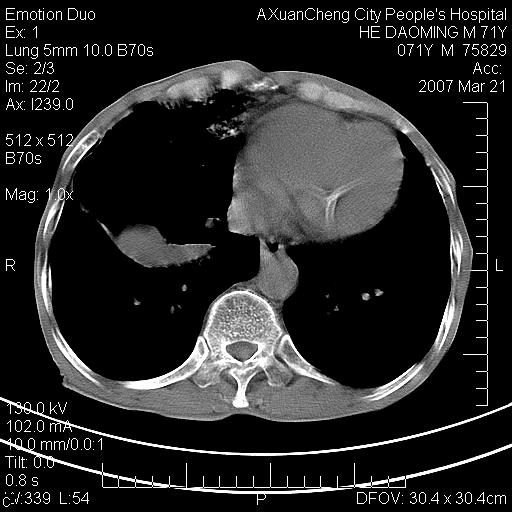

标题: CT7269:[原创] 咳嗽,咳痰,大家讨论右肺病变的部位 [打印本页]

标题: CT7269:[原创] 咳嗽,咳痰,大家讨论右肺病变的部位

1.慢支肺气肿 肺心病 肺大泡;2.叶间裂积液,前胸膜粘连

右侧相当于叶间软组织样密度ct值约50hu,请大家讨论是什么性者病变

右下肺大囊肿伴感染.肺气肿,肺大泡.

考虑:慢性支气管炎合并全小型肺气肿、肺大泡、间质纤维化、感染,右斜裂积液。

考虑慢支,肺气肿,肺大泡,间质纤维化;右侧斜裂液气胸考虑(可能因为肺大泡破裂破入斜裂所致).

考虑病变以右上中肺多发肺大泡为主并感染。请结合临床考虑慢支肺气肿,肺心病。

1双肺慢性支气管炎并全小叶型肺气肿肺大泡2间质性纤维化3右侧斜裂积液

考虑:慢性支气管炎合并右侧全小型肺气肿、肺大泡并感染、双肺间质纤维化,右斜裂积液。

考虑:慢性支气管炎合并右侧全小型肺气肿、肺大泡并感染、双肺间质纤维化,右斜裂积液。右侧斜裂液气胸考虑(可能因为肺大泡破裂破入斜裂所致).